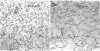

Semicarbazide, a lathyrogen, was given to growing rats to elucidate the consequences of altering the molecular structure of fibrous proteins within the lung. Static pressure-volume (P-V) measurements during deflation of saline-filled lungs showed normal recoil pressure and compliance values within the physiological range of lung volume. Quasi-static P-V measurements were also normal during slow reinflation, even beyond physiological limits to a recoil pressure of 20 cm H20. However, the lungs of experimental rats ruptured at much lower recoil pressures than controls. Histology was normal in lungs fixed at 20 cm H20. In contrast, lungs showed dilation of terminal air spaces, rupture of alveolar walls, and an increase in mean linear intercept in experimental compared with control specimens, when fixed at 30 cm H20. Biochemical analyses revealed reduced cross-linking of lung collagen without change in its total content. There were no detectable changes in the quantity or quality of lung elastin. It is concluded that semicarbazide may selectively impair the maturation of lung collagen and that immaturity of lung collagen is associated with a reduction in the tensile strength of lung tissue, without changes in elasticity within physiological volume limits.